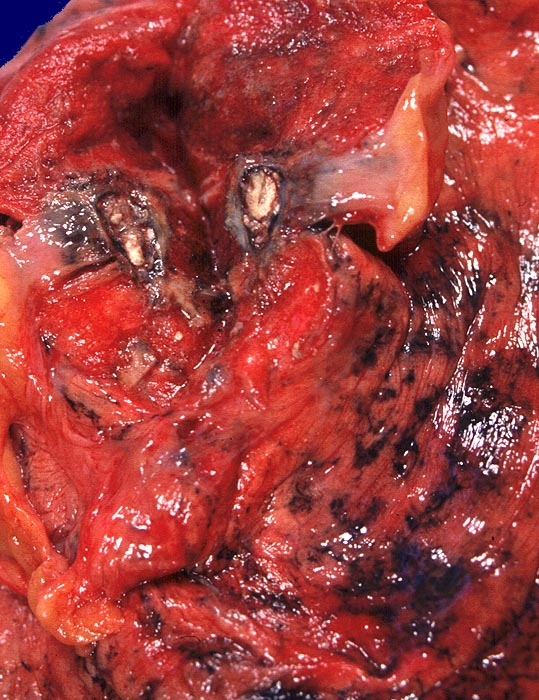

alter tuberkulöser Primärkomplex

Lunge

Kalkkreideherd im apikalen Oberlappen rechts.

Langjähriger Nikotinabusus. Zungenkarzinom bekannt seit einem Jahr. St.n. kleinzelligem Bronchuskarzinom vor 4 Jahren.